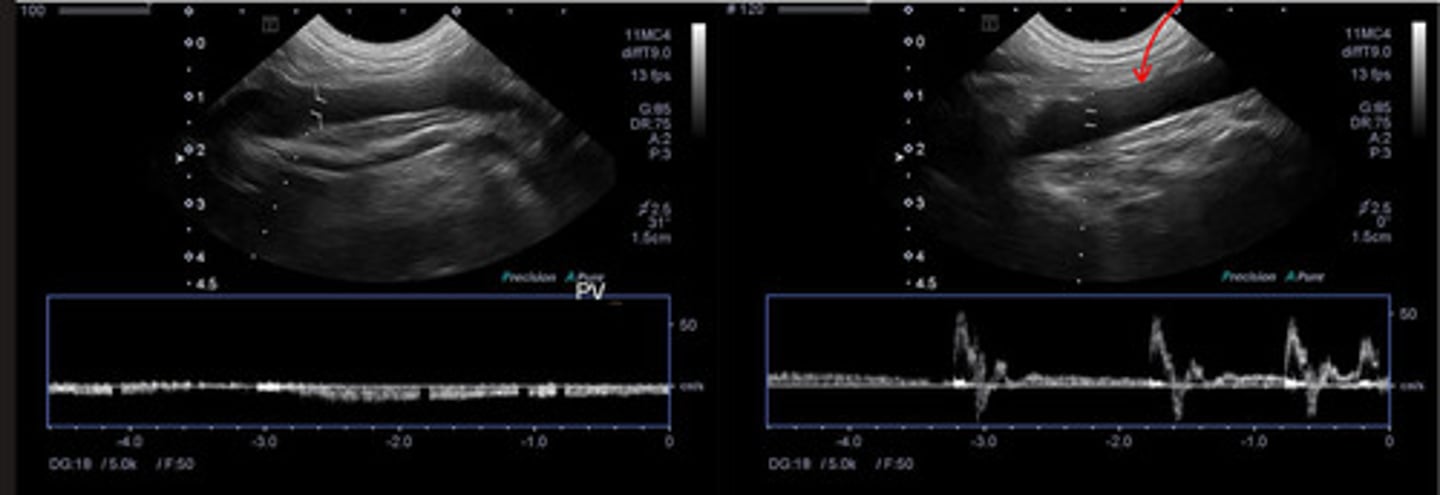

ID vessel indicated by red arrow on a pulsed wave doppler